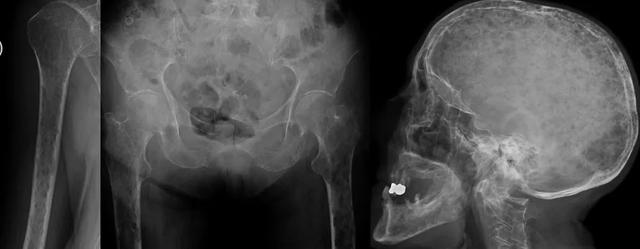

骨髓瘤的一个特征是具有“雨滴颅骨(raindrop skull)”的图案(图7和8)。

图7:骨盆X线片(a):跛行和右侧髋部疼痛的患者,右侧股骨近端明确的溶骨性病变(黄色箭头),皮质破坏。在CT研究(b,c,d和e)中,观察到多个明确边界的皮质下溶骨性病变(红色箭头),提示多发性骨髓瘤。通过骨活检确认诊断。

图8:骨骼调查。多个溶解性病变,具有均匀大小的斑驳图案,颅骨可以观察到“雨滴颅骨”样改变。